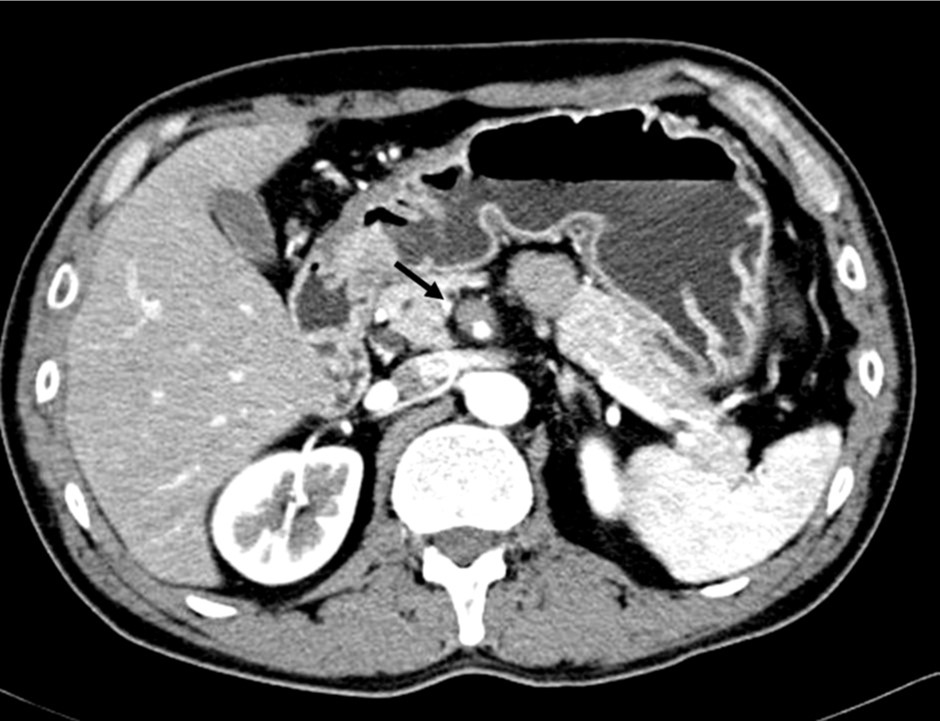

2009년 3월 복부 CT에서 SMA 기시부 하방 2cm 부위부터 5cm 길이의 편심성 혈전이 관찰되고 있으며 혈전이 있는 부위의 동맥 직경이 커져 있음(Fig. 1). 대동맥이나 분지 동맥에 동맥경화증의 소견은 관찰되지 않으며 심장초음파 및 심전도 검사에서 혈전이나 심방 세동은 없었음. CT 소견과 증상을 기준으로 spontaneous isolated SMA dissection으로 진단하였으며 창자의 허혈 소견이 보이지 않고 통증도 악화되지 않아 보존적 치료를 하였음. 2009년 6월 추적 CT에서 false lumen내 대부분의 혈전은 소실되었으나 SMA 기시부 5cm 하방 부위에는 국소적 혈전을 동반한 saccular pseudoaneurysm이 관찰됨. 2009년 8월 시행한 추적 CT에서 pseudoaneurysm의 직경이 2mm 증가함 (Fig. 2). 2009년 9월 시행한 혈관 조영술에서 saccular pseudoaneurysm이 SMA 기시부 5cm 하방부위에 관찰되며 SMA의 국소적 협착이 관찰됨 (Fig. 3). 스텐트와 코일을 이용한 혈관 내 치료 후 시행한 혈관 조영술에서 SMA의 국소적 협착과 pseudoaneurysm은 소실됨 (Fig. 4). 시술 3개 월 후 시행한 추적 CT에서 pseudoaneurysm은 완전히 소실되었으며 SMA는 정상소견을 보임(Fig. 5).

Fig. 2.

Fig. 2. Enhanced CT scan obtained 6 month later reveals improvement of eccentric thrombus, but a saccular pseudoaneurysm is noted in the superior mesenteric artery.